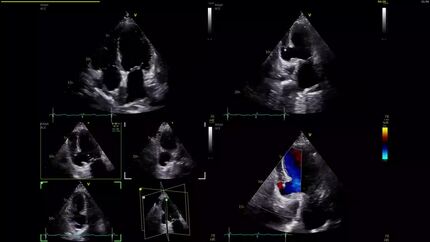

Management and treatment of an acute post-infarction ventricular septal defect in cardiogenic shock

Diagnosis of a ventricular pseudoaneurysm secondary to subacute myocardial infarction